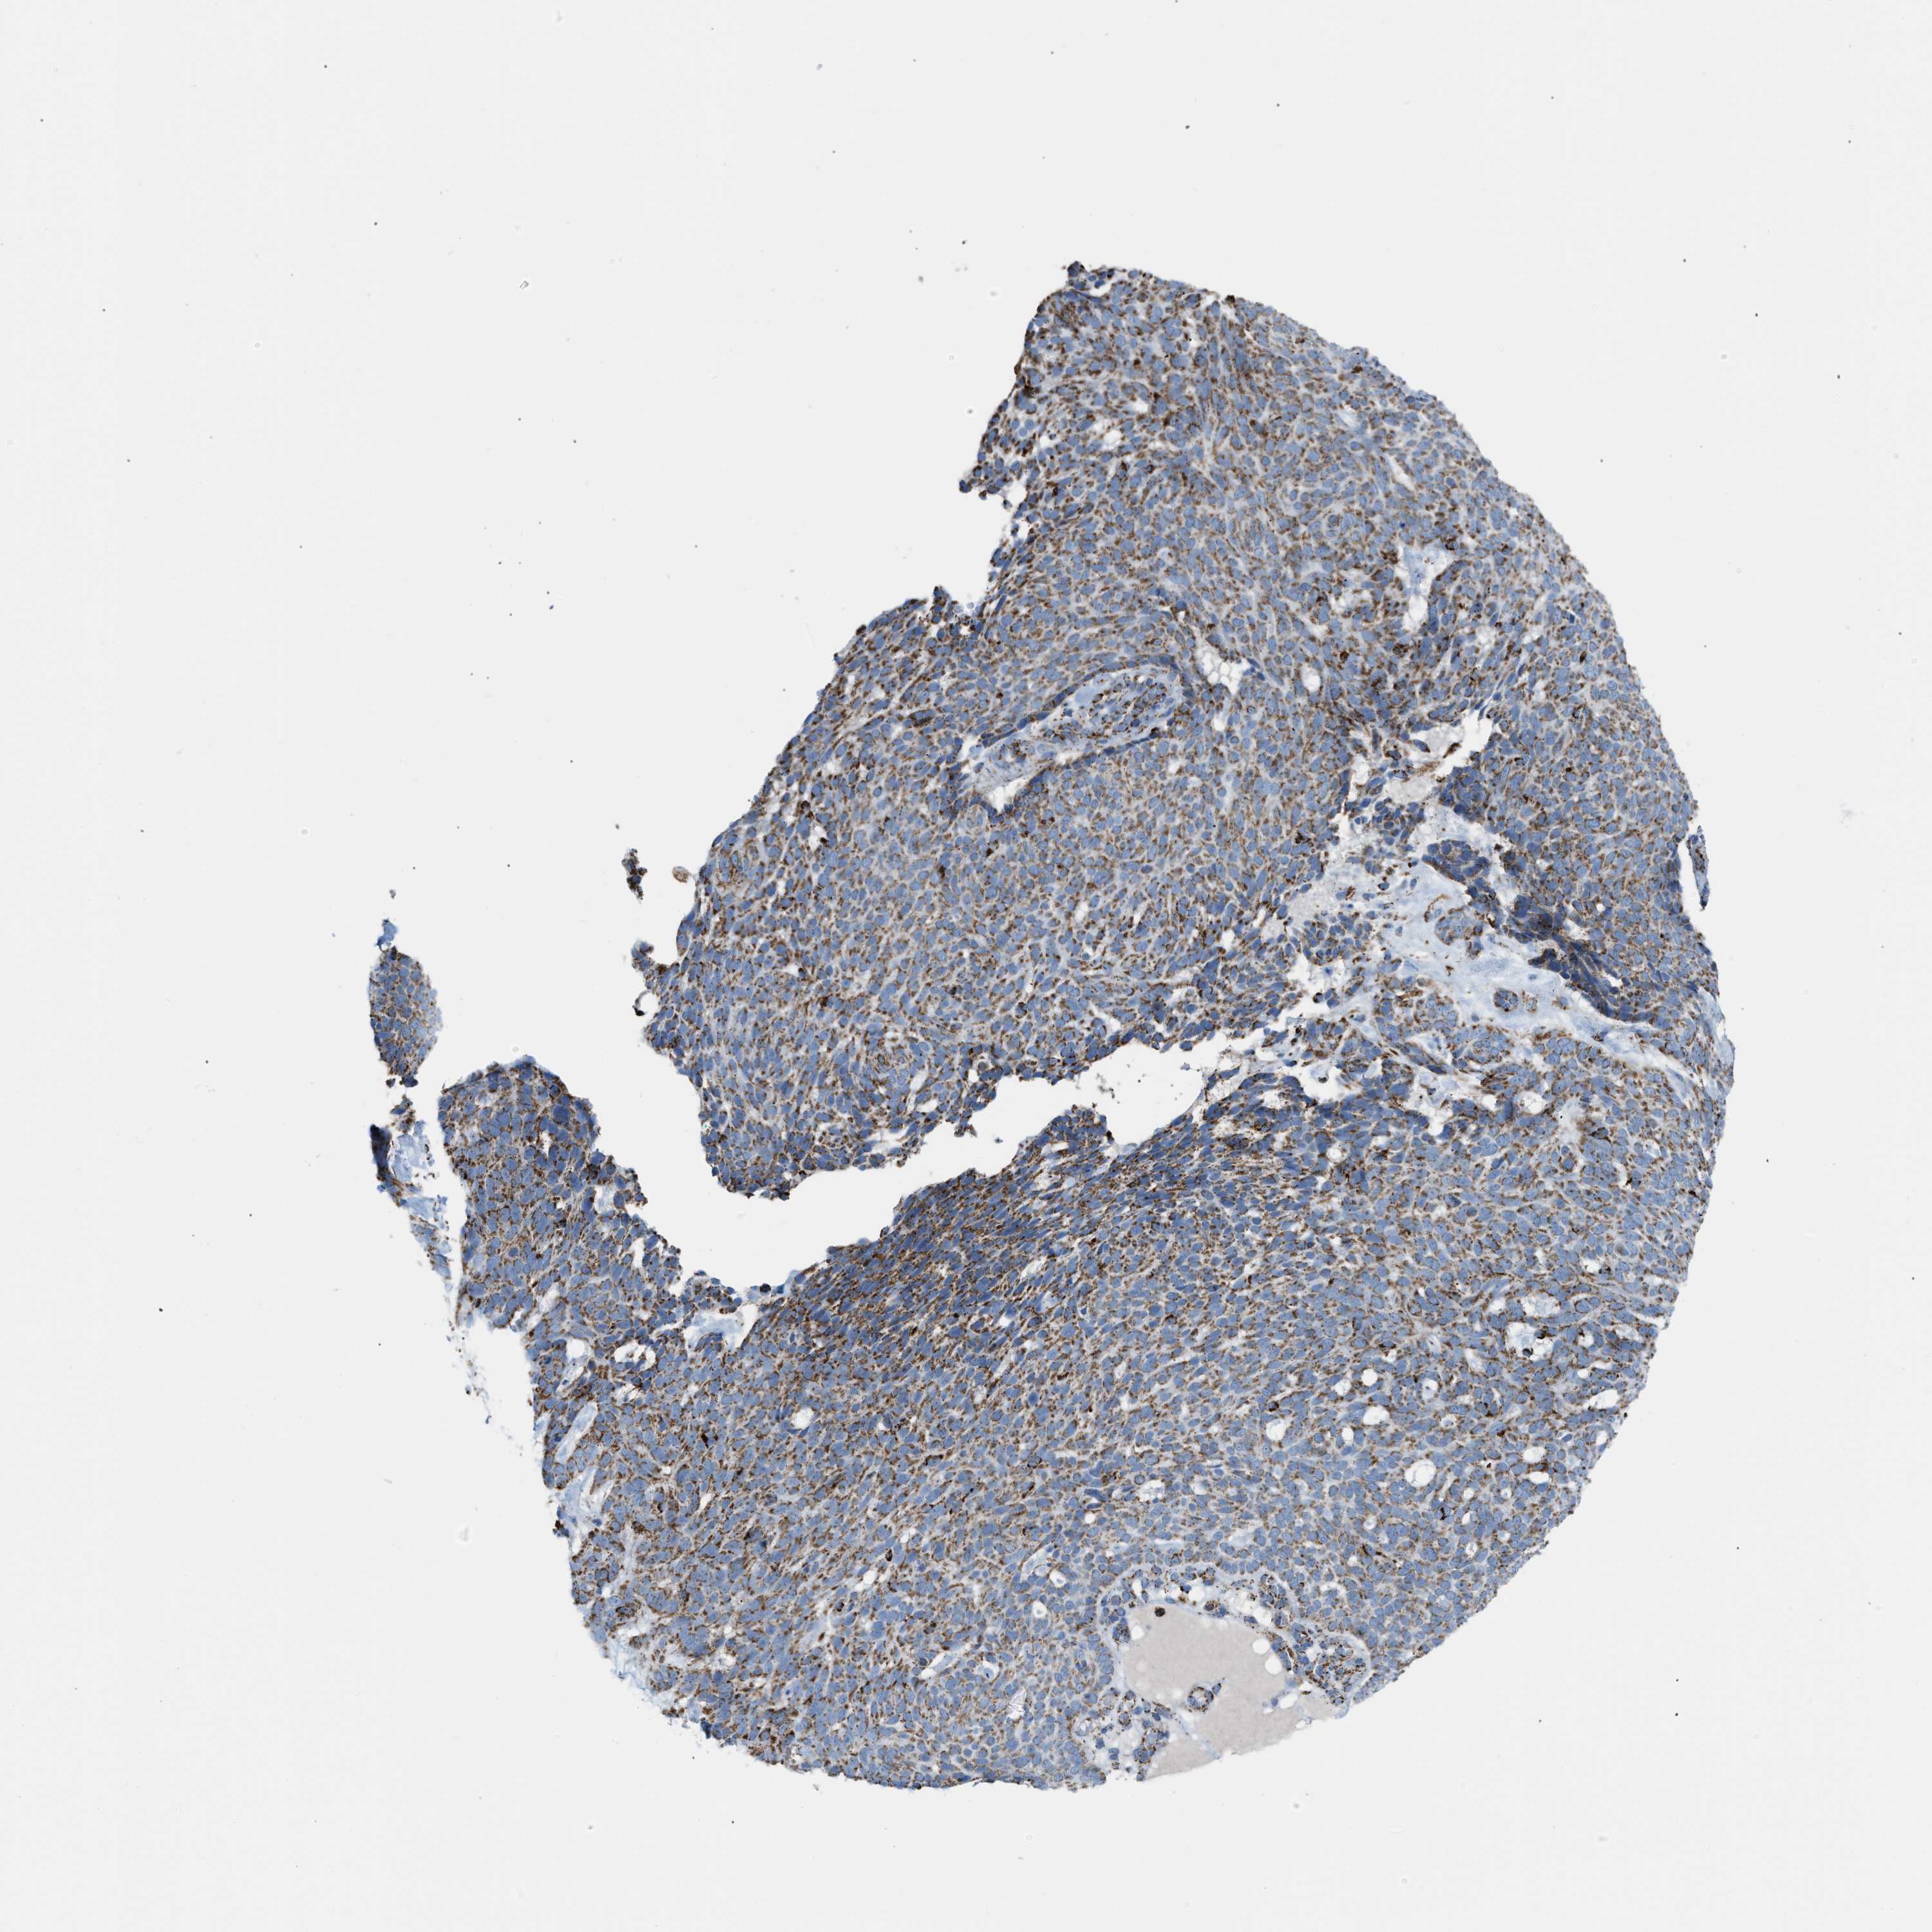

SKIN CANCER - Protein expressioni

A mouse-over function shows sample information and annotation data. Click on an image to view it in a full screen mode. Samples can be filtered based on level of antibody staining by selecting one or several of the following categories: high, medium, low and not detected. The assay and annotation is described here.

Each image is clickable and will lead to virtual microscopy that enables deeper exploration of all samples and also displays staining intensity scores, fraction scores and subcellular localization as well as patient and tissue information for each sample.

Antibody HPA018921

Squamous cell carcinoma, NOS